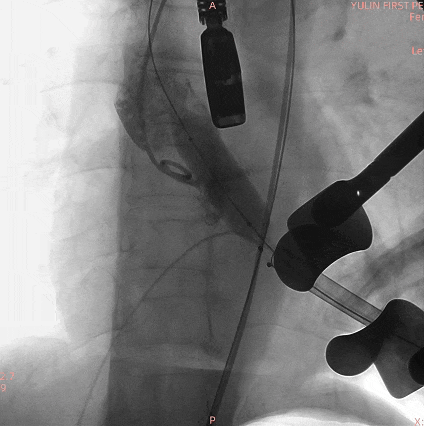

手术过程

通过术前精准评估,患者在全麻下行TAVR手术,DSA和食道超声双重引导,通过穿刺心尖建立工作路径,沿加硬导丝送入19mm*40mm球囊预扩张主动脉瓣,球囊无腰有漏,利用短鞘送入25#RENATUS瓣膜至左室,猪尾巴导管再次造影确认位置。将25#RENATUS瓣膜顺利跨瓣,精准定位,5ATM精确释放,退出输送系统再次行主动脉根部造影,示瓣膜膨胀充分,无瓣口反流,无瓣周漏,冠脉血流正常,术后即刻平均跨瓣压差降至3.62mmHg,超声示术后峰值流速降至0.95m/s。瓣膜释放位置理想、形态及功能良好,瓣叶启闭良好,无外周血管损伤。

术中影像

主动脉根部造影

19mm球囊预扩无腰有漏